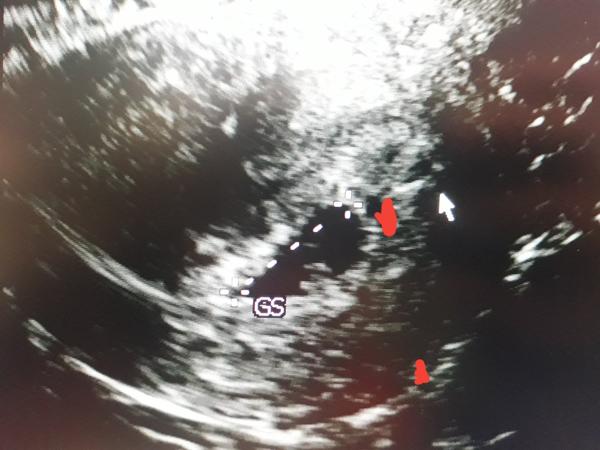

Babyy jedno ci dve? 🤔🤔 doktorke idem az o tyzden ale ako sledujem prvu fotku zo 6.tt na potvrdenie tak sa mi zda ze v strede kde je gestacny vak ktory mi doktorka oznacila kde aj bilo srdiecko drobcekovy, ze pod nim je este jeden 😮🙃